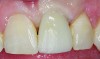

Fig 12. Postoperative photograph of patient shown in Fig 11 after immediate implant placement with immediate loading, tooth No. 9.

Figure 12